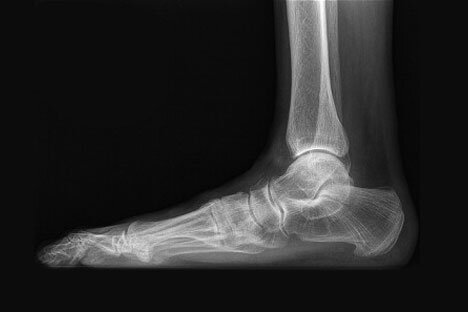

02/17/2020 Flat feet can cause pain, arthritis and tendon degeneration and is something that should be treated from an early age. If your flat foot pain is affecting your quality of life on a daily basis your New York foot doctor may recommend flat foot surgery. The goal of flat foot surgery is to create an arch in the foot and realign your center of gravity to a functionally optimal position. This type of surgery has a long recovery period thus conservative care should always be attempted first. Flat foot surgery is considered a reconstructive surgery and is quite customized to each foot depending on the individual patients bone structure and tendon health. All symptoms, potential procedural/surgical options should always be discussed with your podiatrist after a thorough consultation and examination for an accurate diagnosis and treatment plan.

If you have flat feet, you may have felt symptoms of foot and ankle pain even when participating in normal daily activities. You may have had difficulty walking or running and notice unusual patterns of wear on your shoes. If you have used orthotics or bracing with little success and if you are unable to stand on your toes without pain then surgical treatment by your New York City foot doctor may be recommended.Non-surgical treatments you may try prior to surgery include: